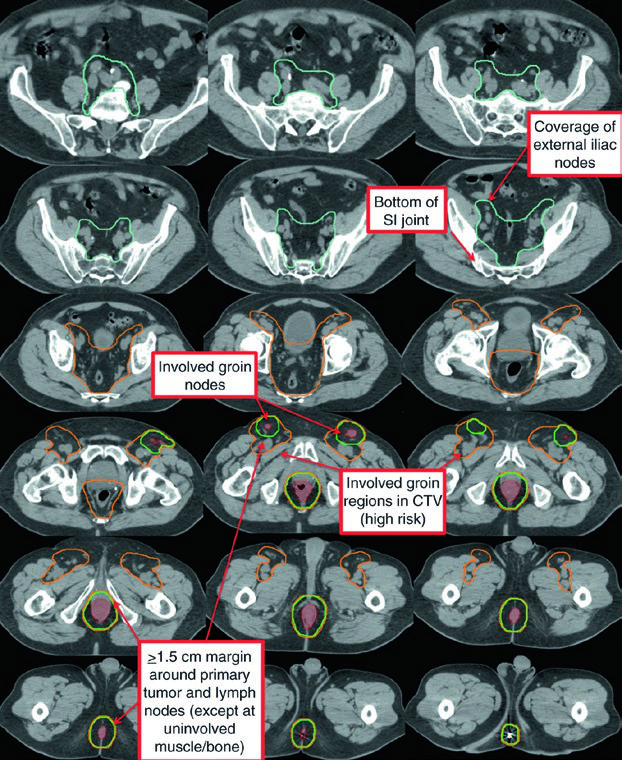

| CTV-P, CTV-N | CTV-P: GTV-P + margem de 1,5–2,5 cm excluindo osso, músculo ou ar não envolvidos. CTV-N: GTV-N + 1,0–1,5 cm excluindo osso, músculo ou ar |

| CTV-HR (alto risco) | Cobre CTV-P, CTV-N, mesorreto inteiro, linfonodos perirretais e ilíacos internos bilaterais inferiores à borda inferior da articulação sacroilíaca. Se inguinais ou ilíacos externos envolvidos, incluí-los. Margem de 0,7 cm ao redor dos vasos ilíacos internos. Margem de 1,8 cm entre vasos ilíacos externos e internos para obturadores. Margem de 1–1,5 cm na bexiga anteriormente |

| CTV-LR (baixo risco) | Cobre linfonodos ilíacos internos não envolvidos superiores à borda inferior da articulação sacroilíaca, ilíacos externos e inguinais não envolvidos. Margens: 0,7 cm ao redor dos vasos ilíacos internos; 1 cm anterolateral nos ilíacos externos; contorno do compartimento inguinal completo |

O atlas de contorno anorretal do RTOG descreve três regiões CTV que devem ser incluídas para todos os pacientes com câncer de canal anal. O Australasian GI Trials Group Atlas detalha sete regiões eletivas. Há desacordos entre as diretrizes RTOG, AGITG e BNG quanto ao contorno dos linfonodos inguinais — dados recentes mostram que 10–29% dos linfonodos inguinais envolvidos ficam fora das bordas nodais recomendadas.

No caso T3N1a com envolvimento inguinal bilateral, PTV-LR e PTV-HR foram tratados simultaneamente a 40 Gy e 45 Gy em 25 frações. Os linfonodos inguinais e ilíacos externos bilaterais foram incluídos no CTV-HR por causa do envolvimento bilateral. Depois, PTV-P e PTV-N receberam boost a 54 Gy em 30 frações totais.